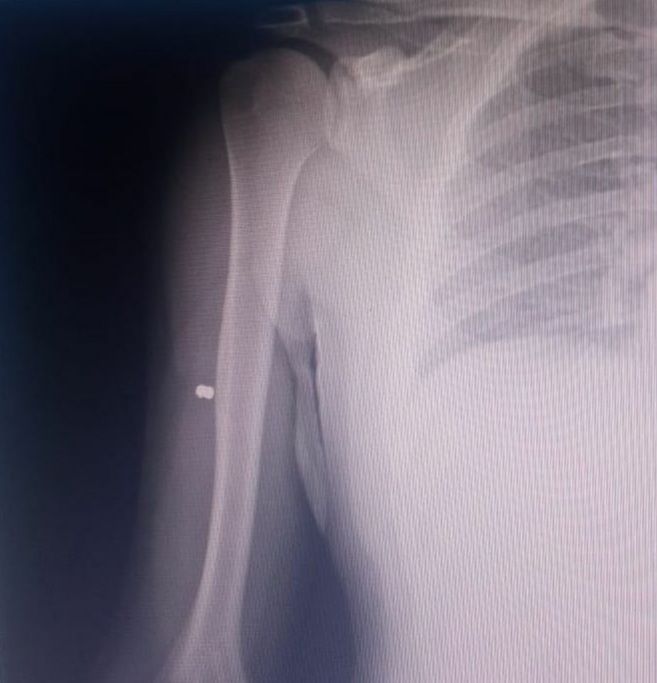

En ese lugar, un músico resultó herido con un balín de un aire comprimido.

La víctima se llama Agustín Rodríguez, de 37 años, quien se estaba presentando en el deck exterior de la cervecería, y que terminó lastimado en un brazo y asistido en el Hospital Privado del Sur.

Se trata de Santiago Boughen, médico hematólogo de 42 años, quien quedó imputado por lesiones leves y a quien se le allanó el domicilio en busca del arma, con resultado negativo.